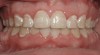

Figure 3 “Before” photograph of an adult patient with significant periodontal disease and recession with some teeth that historically might have been considered “hopeless.”

Figure 3

Figure 4 “After” photograph of the same patient in Fig 3 showing the significant benefit of orthodontic treatment on the health of the teeth and gums.

Figure 4